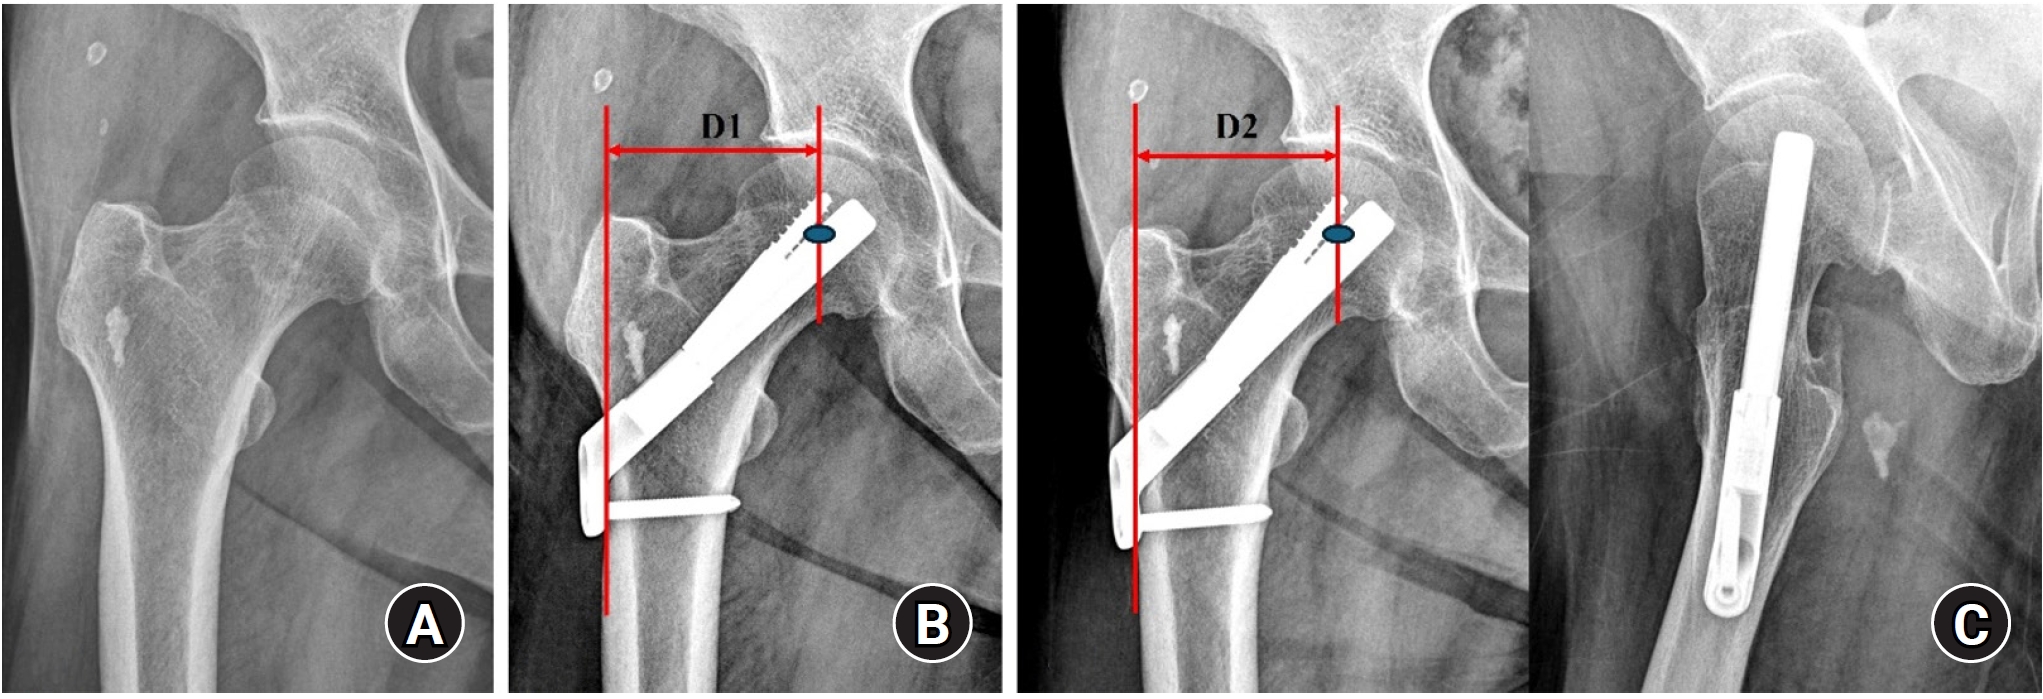

Radiological assessment

Standardized anteroposterior and lateral radiographs of the hip were obtained immediately postoperation and at each follow-up visit (6 weeks, 3 months, 6 months, 1 year, and annually thereafter). Radiological union was defined as the disappearance of the fracture line, accompanied by the absence of pain on full weight-bearing. Femoral neck shortening was calculated as the difference in the distance from the center of the femoral head to the lateral cortex of the femur between the immediate postoperative and final follow-up radiographs (Fig. 2). Femoral neck shortening was measured independently by two experienced orthopedic surgeons, and the average of their values was used for the analysis. Complications, including fixation failure (e.g., screw cut-out or excessive sliding), AVN of the femoral head, nonunion, and the need for revision surgery, were investigated.

Radiological outcomes

At the final follow-up, the union rate was 87.5% (21/24) in the FNS group and 95.8% (23/24) in the DHS group, with no statistically significant difference between the two groups (P=0.296) (Figs. 2, 3). The mean femoral neck shortening was measured at 6.1 mm in the FNS group and 5.9 mm in the DHS group, and no significant difference was observed (P=0.427).

Fig. 2.

(A, B) A 67-year-old female patient with a right femoral neck fracture (Garden type 1) treated with the femoral neck system. (C) The postoperative 4-year radiograph shows a well-healed fracture site and no complications related to the implant. Femoral neck shortening (D2‒D1) was calculated as the difference in the distance from the center of the femoral head to the lateral cortex of the femur between the immediate postoperative and final follow-up radiographs.

Fig. 2. (A, B) A 67-year-old female patient with a right femoral neck fracture (Garden type 1) treated with the femoral neck system. (C) The postoperative 4-year radiograph shows a well-healed fracture site and no complications related to the implant. Femoral neck shortening (D2‒D1) was calculated as the difference in the distance from the center of the femoral head to the lateral cortex of the femur between the immediate postoperative and final follow-up radiographs.